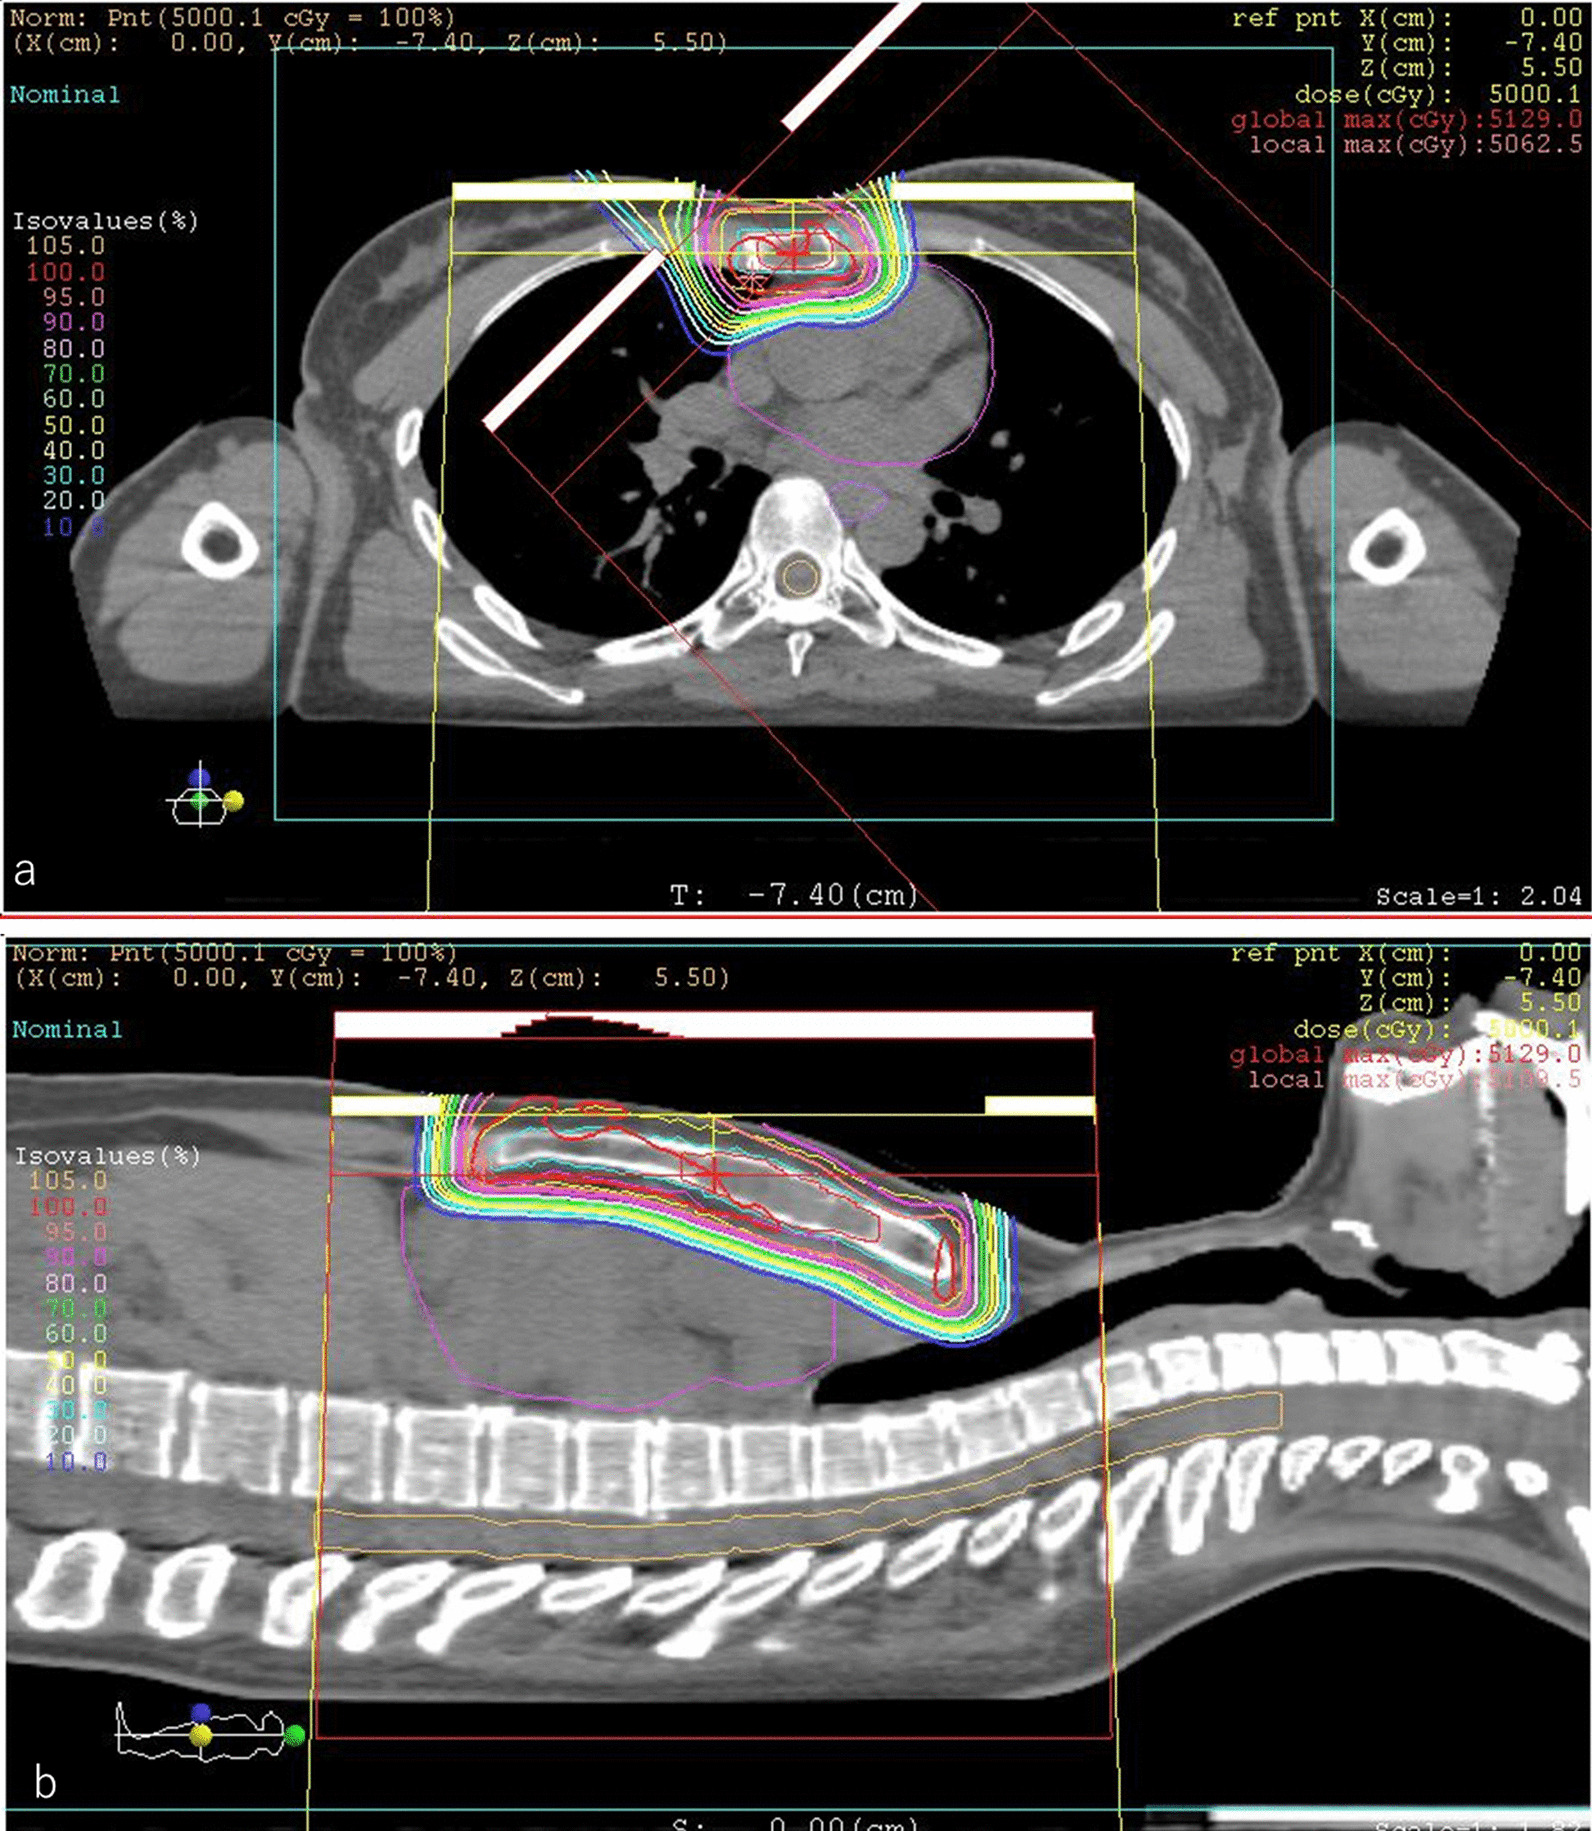

Fig. 3.

Dose distribution of initial proton beam therapy (PBT) in an axial field (a) and a coronal field (b). The daily PBT fractions were 2.5 relative biological effectiveness (RBE) for PTV, receiving a total dose of 50 Gy RBE. The gross tumor volume was 16.21 cm3. The clinical target volume was 60.44 cm3, and the planning target volume was 147.31 cm3